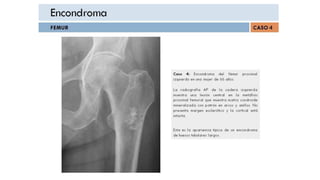

ENCONDROMA

Encondroma .- Consideraciones Generales

•Tumor cartilaginoso benigno que se desarrolla en cavidad medular

•Generalmente solitarios, (puede ser múltiple)

•Surgen de restos ectópicos de cartílago hialino

•Ocurren principalmente en la segunda o tercera década

•El sitio más común es pequeños huesos de manos y pies

• La mayoría ocurre en la falange proximal

•El tumor más común de la mano

• También ocurre en el húmero, el fémur, la tibia y las costillas

•En huesos largos, su calcificación es similar a un infarto óseo intramedular

• Infartos de hueso tienden a tener margen esclerótico bien circunscrito